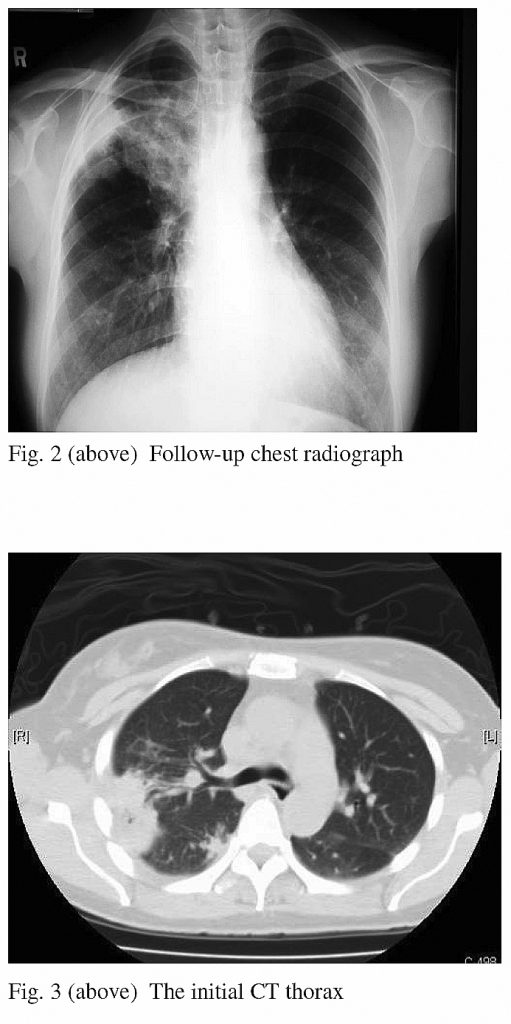

A contrast computed tomography (CT) of the chest revealed consolidations over apical and posterior segments of right upper lobe and a tiny calcified granuloma in the right middle lobe, with no mediastinal or hilar lymphadenopathy. (Fig. 3)